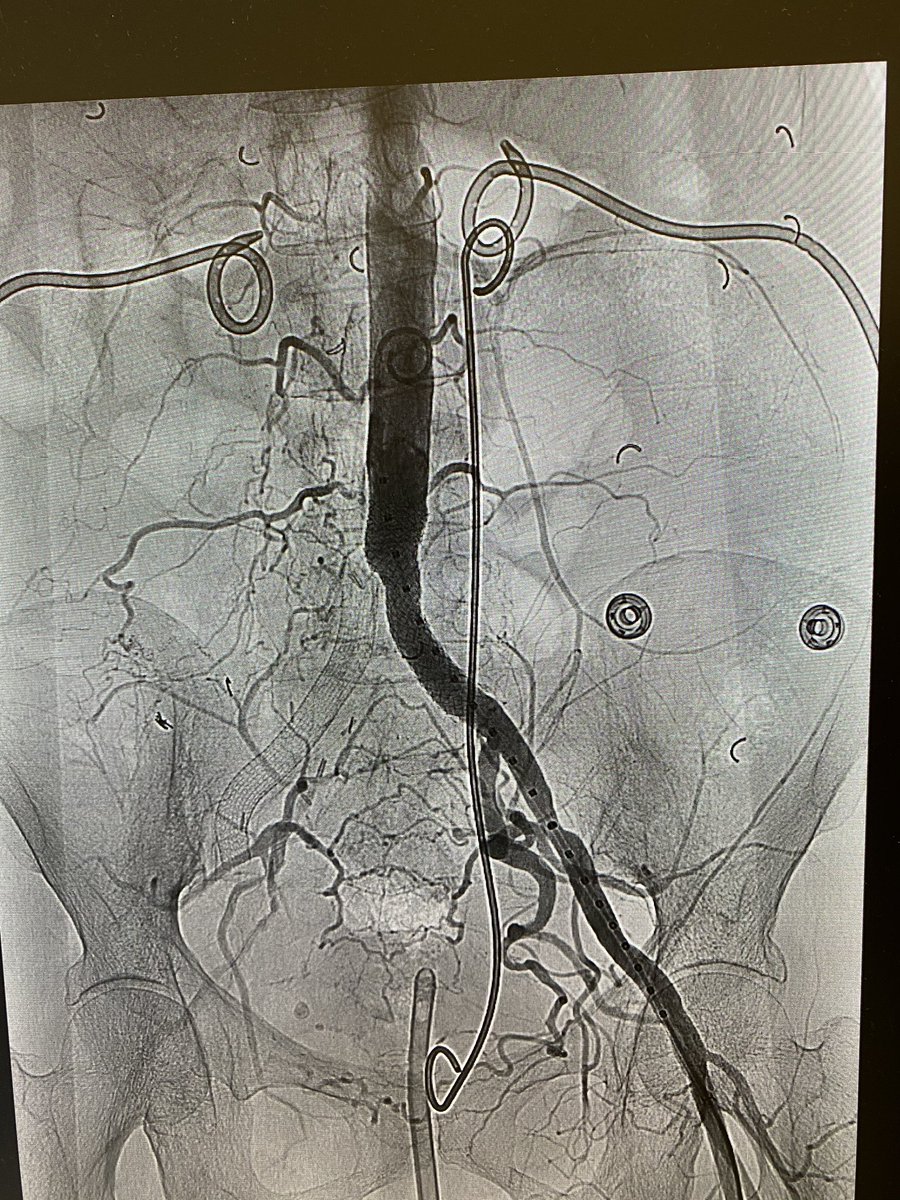

Malignant SVC syndrome w/ stridor; central upper extremity/IJ #DVT; @InariMedical FlowTriever for acute thrombus and ClotTriever for more than expected subacute/chronic; @BDandCo #Venovo for reconstruction @RonaldWinokurMD @TJUHospital @JeffersonRads @kekstero78 @carin_gonsalves